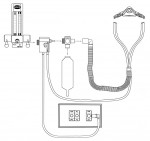

Treatment can now be accomplished with minimal discomfort. New nitrous oxide analgesia systems can reduce anxiety. They should have a failsafe flowmeter, double-mask scavengers with scavenger breathing coaxial tubing and automatic vacuum switches to assume that when gas flows the vacuum is on (Figure 3). This reduces risk and can ensure safety for the patient and staff.